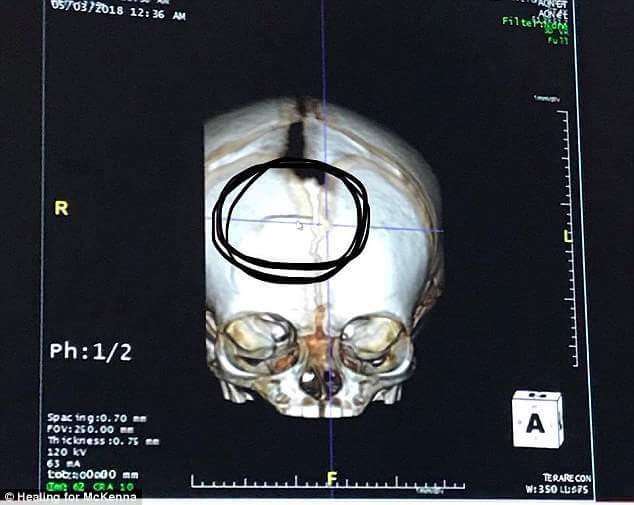

▼強力的衝擊將麥克納的頭骨都打到裂開,大腦有兩處出血,也多次癲癇發作,目前仍需要深層麻醉和依賴呼吸機來呼吸。